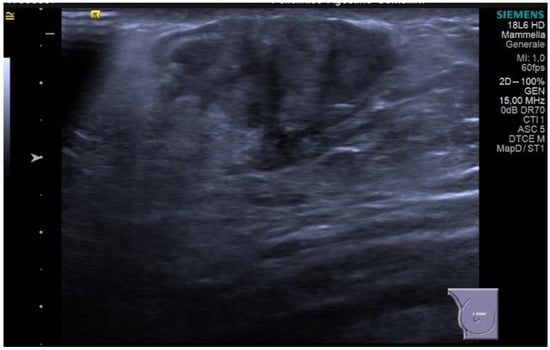

IDC typically originates from the terminal duct–lobular unit [28,29]. Clinical features include a palpable unilateral retroareolar mass with nipple retraction and skin thickening [28,29]. Around 25% of cases may present with bloody nipple discharge [28]. IDC can be associated with ductal in situ components in up to 50% of cases [30]. Mammographically, IDC appears as a retroareolar irregular high-density mass with spiculated or micro-lobulated margins [30,31]. Unlike in women, IDC in men is rarely associated with microcalcifications due to the involution of the ductal system caused by the absence of estrogen and progesterone stimulation [28,29]. Ultrasonography reveals solid, hypoechoic, and irregular masses with margins ranging from microlobulated to spiculated [32]. Papillary carcinoma (PC) is the second most common invasive subtype of MBC and has a higher incidence in men compared to women [33]. PC is characterized by neoplastic proliferation of cells with fibrovascular stalks lacking an intact myoepithelial cell layer [34]. It typically presents with bloody nipple discharge and occurs in the subareolar region. Mammographically, PC may exhibit well-circumscribed or spiculated margins, while ultrasound imaging may reveal a dilated duct or cyst, often appearing as a complex cyst with solid papillary projections along the cyst wall [35,36] (Figure 8).

Figure 8.

Invasive papillary carcinoma in a 59-year-old man with bloody nipple discharge. Magnification of mediolateral oblique view of the right breast (A) shows a focal high-density mass with well-circumscribed margins (red circle). Ultrasound (B) shows a complex cyst with mixed solid and cystic morphologic features.